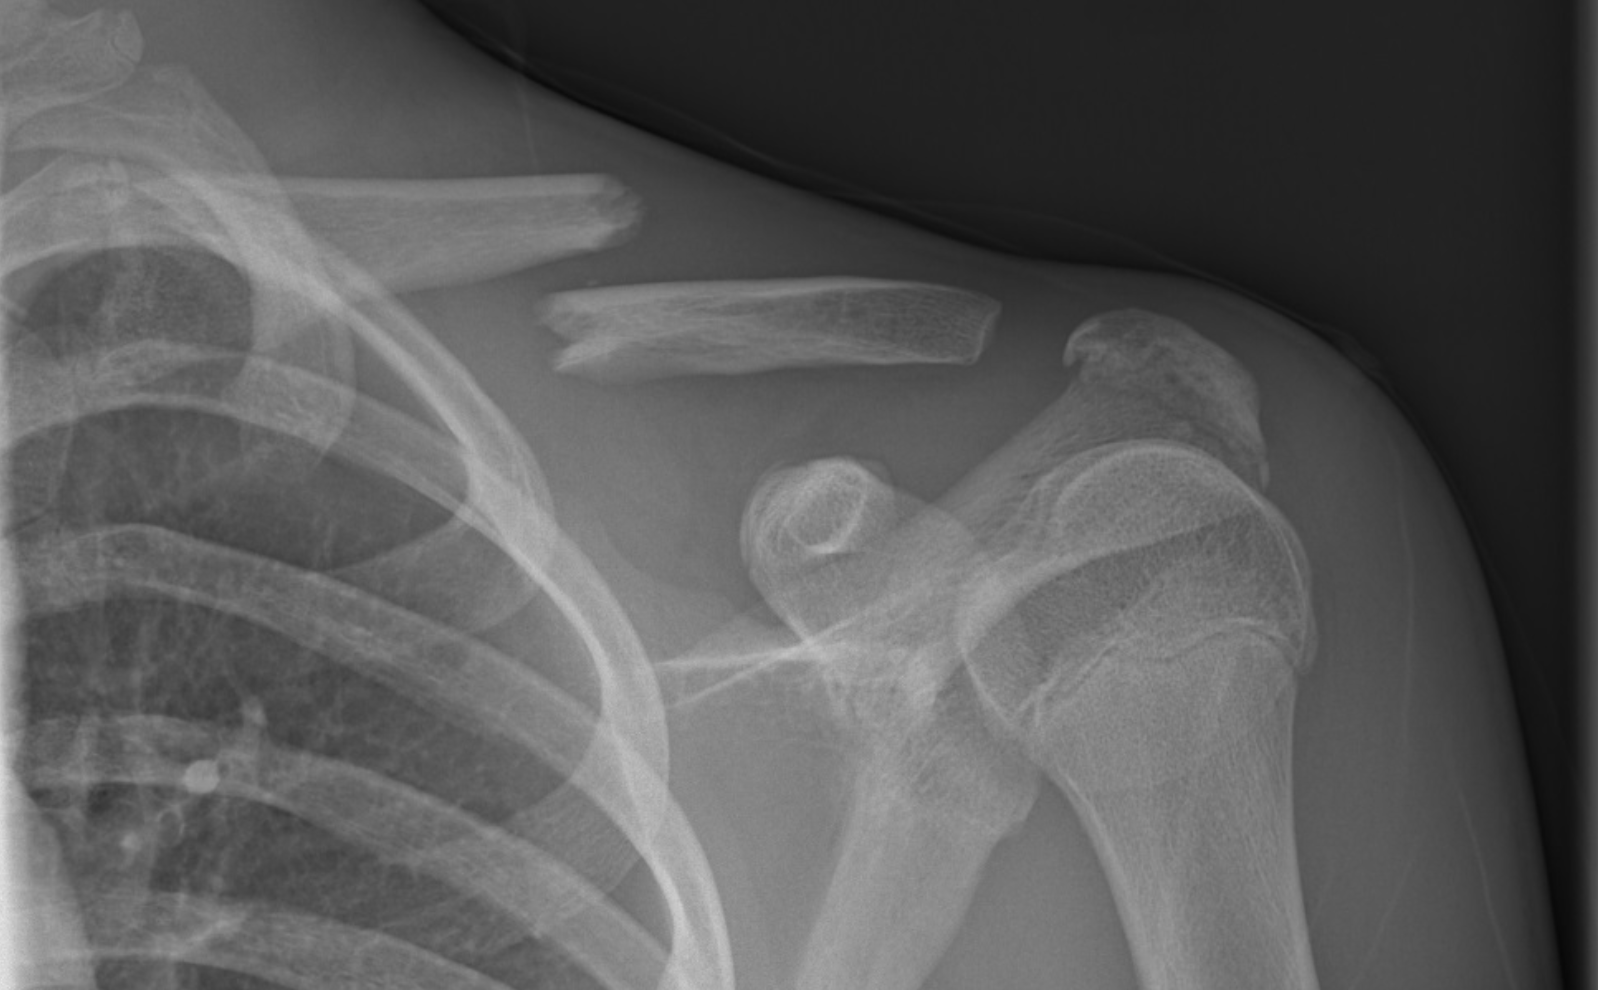

X-ray image of a shoulder showing fractured clavicle, scapula, and humerus bones.

Clavicular Fracture

A clavicular fracture is a common injury caused by direct trauma to the shoulder or a fall onto the arm, leading to a break in the collarbone.